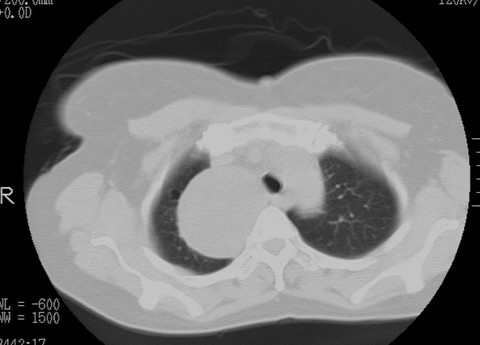

以下是引用随光逐影在2010-3-1 8:36:00的发言:[br]右上纵隔囊性占位性病变,考虑支气管囊肿,不排除神经源性肿瘤。